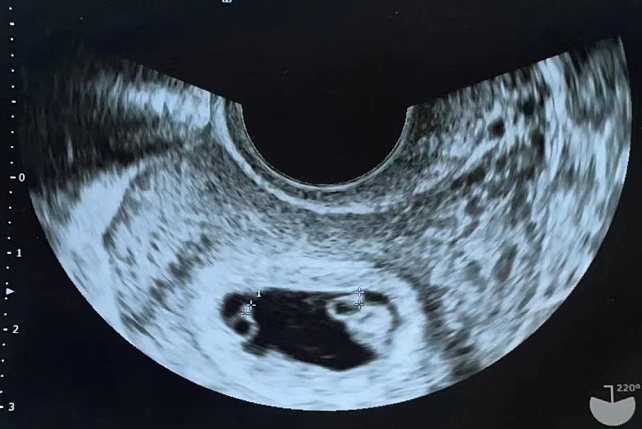

1、同卵双胞胎

在妊娠早期,同卵双胞胎会由一个妊娠囊发育成两个妊娠囊,所以同卵双胞胎在早期B超检查中一般显示为一个妊娠囊中有两个胎心。